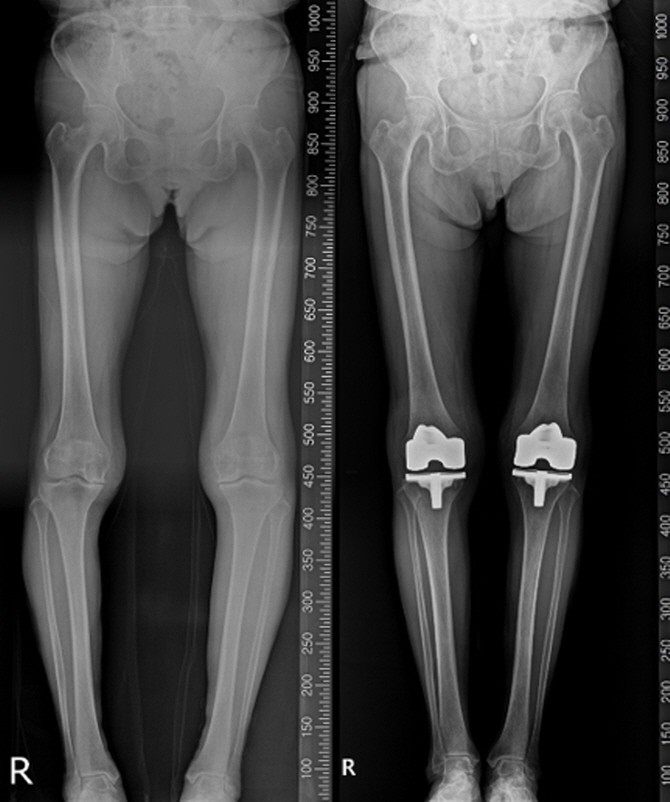

절개·전극선 없는 치료…마이크라2가 연 심박동기의 새 기준